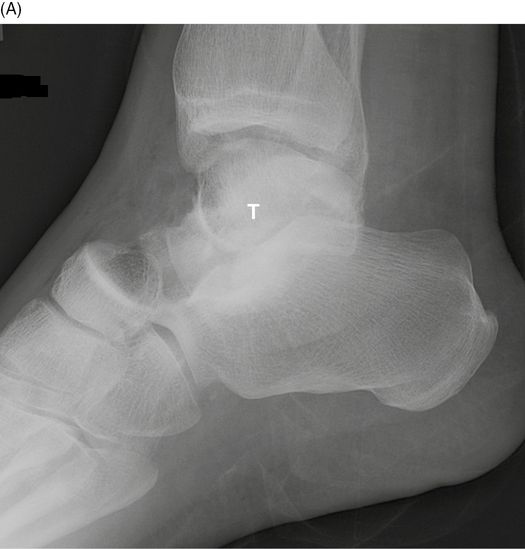

Avascular Necrosis of the Talus A Pictorial Essay RadioGraphics

Avascular necrosis is the death of bone tissue due to a lack of blood supply. Learn how they're diagnosed and treated as well as what to expect for recovery. In many cases, though, blood flow resumes and the prognosis is a healthy one. Because the talus is so important for ankle movement, a. In serious cases, when the blood vessels don’t recover, bone cells die and the ankle can collapse. Also called osteonecrosis, it can lead to tiny breaks in the. Talar avascular necrosis happens when the talus bone, the bone in the center of your ankle, loses some of its blood supply. The talus is predisposed to avascular necrosis (avn), or bone death due to ischemia, owing to its unique structure, characteristic extraosseous arterial sources, and variable intraosseous blood supply. This can lead to pain. Despite advances made in their management, they.